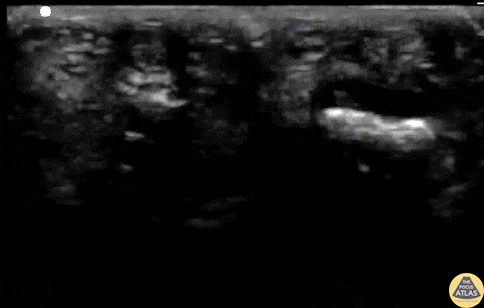

21 y/o F with 1 day of pointer finger pain. 4/4 Kanavel's signs - pain with passive extension, percussion tenderness, sausage digit, flexion posture of finger. Consultant is "unimpressed" and wants the patient on observation. Waterbath POCUS performed and demonstrates a fluid collection between the tendon and the bone (digit on left). Normal digit is on right. POCUS changed management and the patient went to the OR with confirmed FTS. Matthew Riscinti, MD - Kings County/SUNY Downstate Emergency Medicine